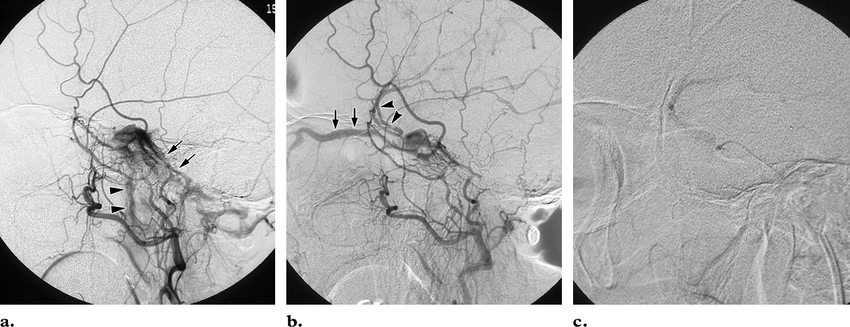

Dural arteriovenöz fistüllerde (Dural AVF) endovasküler (damar yoluyla) tedavi nasıl yapılır?

Endovasküler tedavinin amacı lezyonun tam tedavisi, yüksek riskli fistülün düşük riskli hale getirilmesi veya semptomların giderilmesi olabilir. Tam ve kalıcı tedavi ancak tüm besleyici arterlerin veya venöz drenajın embolik (tıkayıcı) materyal ile tıkanması ile olur.

Kavernöz sinüs fistüllerinde (indirekt) aynı taraf, eğer kateterize edilemezse karşı taraf inferior petrozal sinüs kateterize edilerek embolizasyon yapılabilir. Embolizasyona bağlı komplikayon oranı % 2-10 arasında değişmektedir.